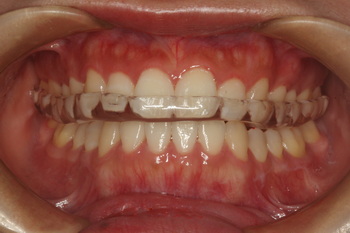

ブラキシズム患者での長期使用を前提とするアクリルスプリント,保険請求では口腔内装置1,

(印象42+咬合採得187+装着1650+調整120)耐摩耗性が高くきれいな見た目が続きます.

デメリットは装着時に調整が必要で,ぴったり合わせるには,少しコツが必要です.